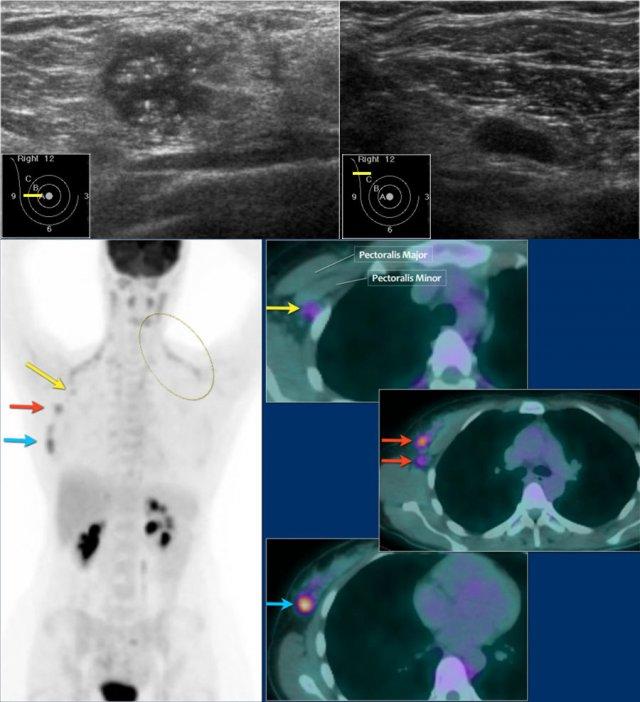

Dưới đây là ví dụ về một bệnh nhân ung thư vú giai đoạn tiến xa.

Siêu âm tuyến vú phát hiện tổn thương giảm âm kích thước 18mm với bờ không đều và vôi hóa vi thể.

Siêu âm nách phát hiện một hạch bạch huyết không còn rốn hạch mỡ.

Chọc hút tế bào bằng kim nhỏ (FNA) được thực hiện, và cả khối u lẫn hạch bạch huyết đều dương tính với adenocarcinoma.

Tổn thương được phân giai đoạn lâm sàng là cT1N+. PET-CT được thực hiện tiếp theo.

Trên hình PET-CT phía trên, một hạch bạch huyết mức độ II dương tính nằm ngay bên dưới cơ ngực bé (mũi tên vàng).

Nhiều hạch nách được phát hiện nhưng không có di căn toàn thân.

Mô mỡ nâu bình thường được nhìn thấy dọc theo cơ cổ và cơ vai ở cả hai bên (vòng tròn).

Bệnh nhân này được lên kế hoạch điều trị tân bổ trợ và sinh thiết được thực hiện để xác định độ mô học, thụ thể nội tiết và khuếch đại HER-2-neu.